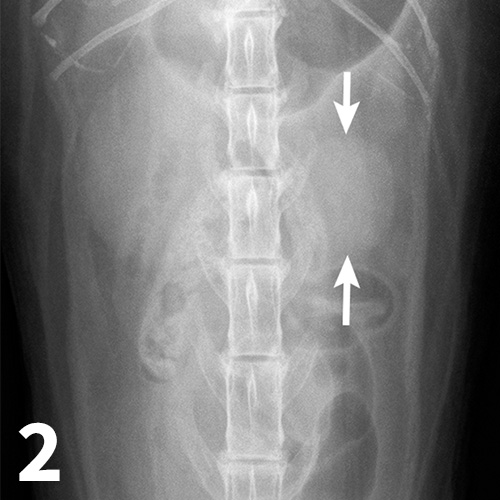

Imaging the Urinary Tract Clinician's Brief Measuring Kidney Length When fully developed, the kidneys are roughly the size of a fist. Normal kidney size range in children based on age, percentiles, and upper bound of renal length. Based on the results of a multicenter study, in which lms. Measurement of renal size by ultrasound is essential when evaluating patients with possible renal disease. Kidney size is an important factor. Measuring Kidney Length.